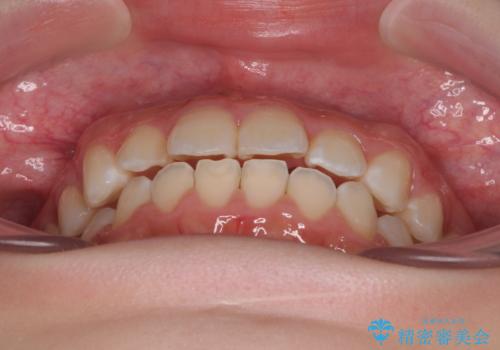

- 上下前歯部のデコボコを気にして来院された患者様です。

叢生は軽度であったため、マウスピースでもワイヤー装置でも対応可能でしたが、マウスピースを長時間使用する自信がないとのことでワイヤー装置にて矯正治療を行うこととしました。

叢生が軽度であったため、僅か半年で装置を除去することができました。